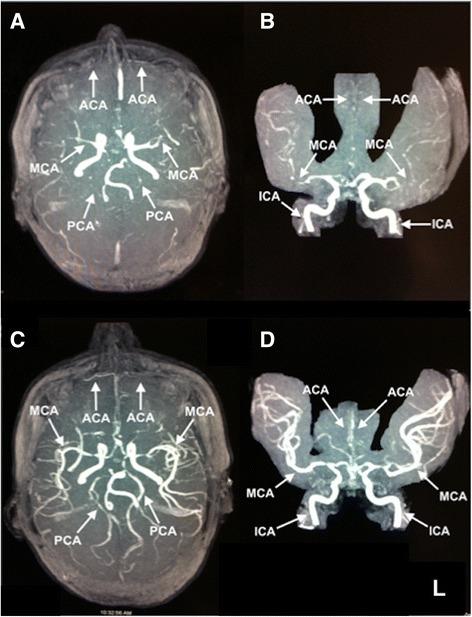

We report a case of a 35-year-old Yemeni woman who presented with headache and focal neurological deficits that occurred 10 days after delivery, with segmental narrowing of cerebral arteries on angiography. She had significant clinical and radiological improvement on follow-up.

我们报告一例35岁也门女性病例,该患者产后10天出现头痛和局灶性神经功能缺损,血管造影显示脑动脉节段性狭窄。随访时其临床和影像学表现有显著改善。